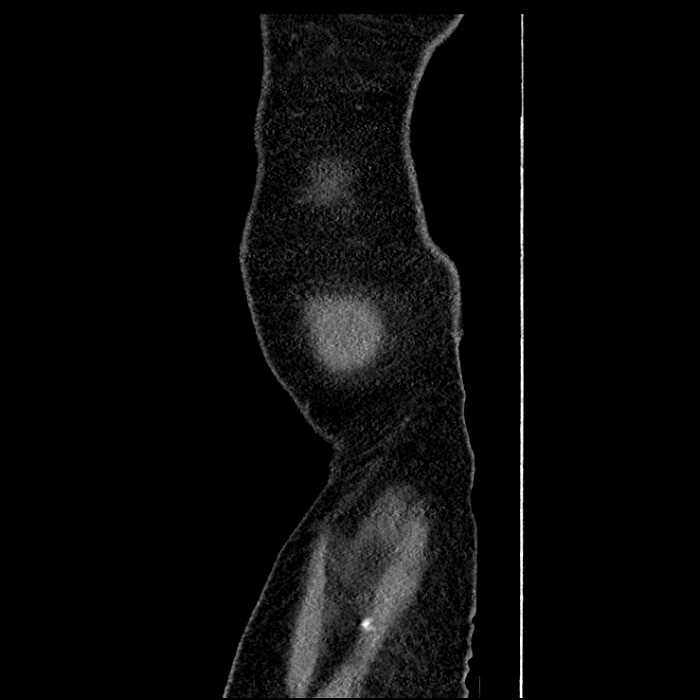

• The classic CT imaging appearance is a double target sign with internal low density surrounded by an internal enhancing rim (capsule) and a low density external rim (edema)

Hepatic abscess showing the double target sign with low density internally surrounded by a thin inner enhancing rim (red arrow) and ill-defined outer low density rim (yellow arrow). Blue arrow indicates an internal septation. Red arrows: additional smaller subcapsular abscesses. Red arrow: focal contained perforation associated with diverticulitis.